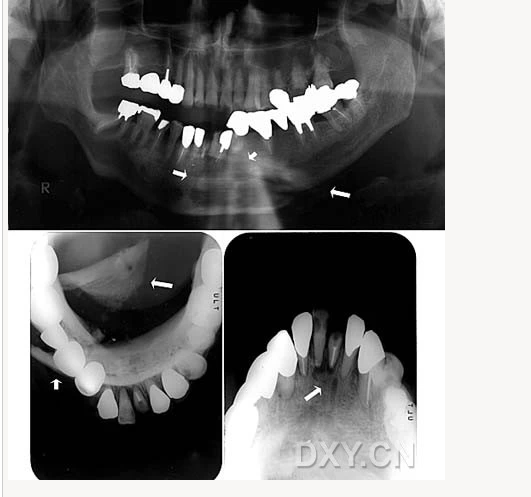

涎石病

骨髓炎

頜骨骨折